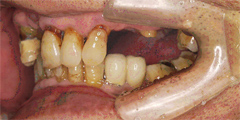

骨が無い部分にGBR(骨再生手術)を行い、インプラントと骨をくっつける

写真(2)

骨が再生されインプラントときちんとくっついている状態の写真です。